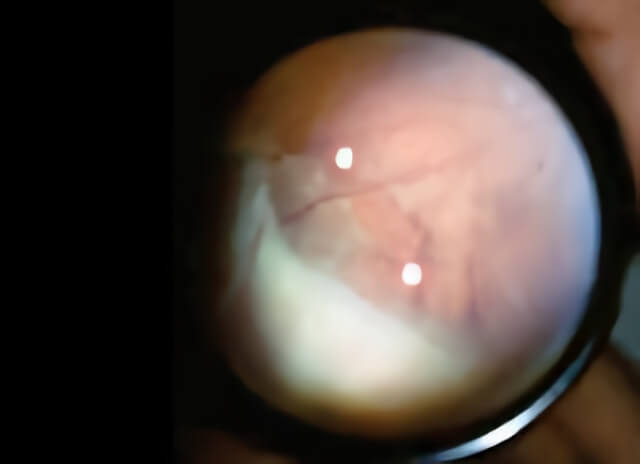

In this photograph, the inflammatory debris from pars planitis is visible as a “snowbank” on the retina in the lower left portion of the image.

Once the pars plana develops inflammation, large clusters of cells and debris disperse into to the center of the eye and lodge in the vitreous, normally a crystal clear jelly-like substance that occupies the central cavity of the globe. These opaque clumps cast shadows onto the retina and are perceived as “junk” floating in the visual field. This debris is readily visible to your ophthalmologist during your examination. The medical term for this is “vitritis” and its effects can reach the lens and iris, leading to cataract and scarring, and to the central retina, leading to swelling of the macula and blurred vision. The swelling of the retina caused by pars planitis is known as cystoid macular edema.

In pars planitis, a form of uveitis, inflammatory debris forms in the vitreous cavity located in the interior of the eye. This debris can block the vision or be seen by the patient as “floaters.”